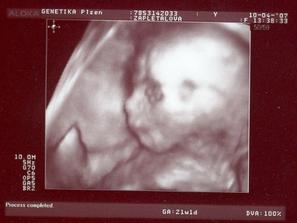

Tomášek

Tomášek se narodil přesně 3 týdny před termínem v Plzni na Slovanech 30.7.2007 Měřil 50 cm a vážil 2900g